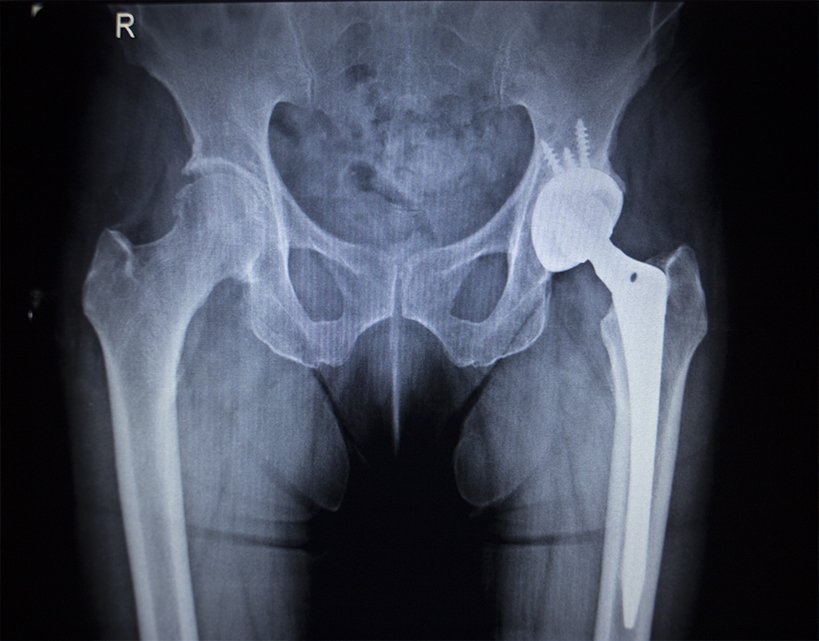

La prótesis de cadera es la sustitución de la articulación dañada de cadera por una articulación artificial. Puede ser total, parcial, así como recambio protésico.

En este tipo de intervenciones se reemplaza unas superficies articulares dañadas de la cadera (fémur y pelvis ) por otras superficies artificiales.

Esta cirugía se realiza con anestesia raquídea o locoregional de piernas hacia abajo, dependiendo de cada caso. La duración puede rondar entre 40 y 60 minutos, según los casos. El ingreso en el hospital tiene tiene una duración media de 3-4 días, dependiendo de la intervención.

Esta técnica fue diseñada con el objetivo de perfeccionar la colocación anatómica y alineamiento de los implantes protésicos mediante un sistema de telenavegación tridimensional.

Con este sistema de alta precisión, y con la ayuda de sistemas informáticos, el cirujano es capaz de perfeccionar la colocación de la prótesis obteniendo una mayor estabilidad osteoligamentosa.

Esta técnica sirve para las prótesis tanto de rodilla como de cadera, es 100% recomendable ya que permite a los especialistas tener la máxima precisión durante la cirugía.